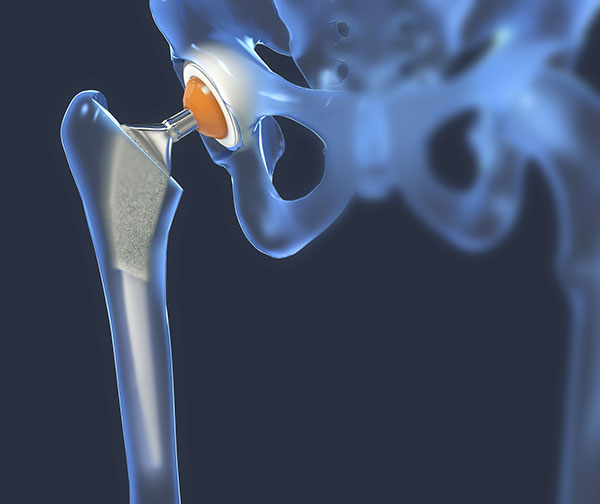

Hip Replacement

hip replacementThe hip joint is a ball and socket joint, that consists of cartilage on the ball of the upper end of the thigh bone (femur) and another layer within your hip socket. This cartilage serves as a cushion and allows for smooth motion of the hip. Arthritis is a wearing away of this cartilage, which eventually wears down to bone. Rubbing of bone against bone causes pain, swelling and stiffness. When non-operative treatment fails to control the discomfort and stiffness from arthritis of your hip, your surgeon may recommend total hip replacement surgery.

Total hip replacement removes the arthritic ball of the upper thigh bone (femur) as well as the damaged cartilage from the hip socket. The ball is replaced with a prosthetic ball and metal stem that is fixed solidly inside the thigh bone (femur). The socket is replaced with a prosthetic liner that is fixed inside a metal shell. This creates a smoothly functioning joint. The implants are designed to restore function and eliminate as much discomfort as possible while allowing you to return to a more active lifestyle.

Rehabilitation and walking begin the day after surgery, and hospital stay is typically just one overnight. Therapy will begin in the hospital and usually continues after discharge with home PT. Joint replacement surgery of the hip has been extremely successful in helping patients with arthritis return to their normal activities and relieve their discomfort.